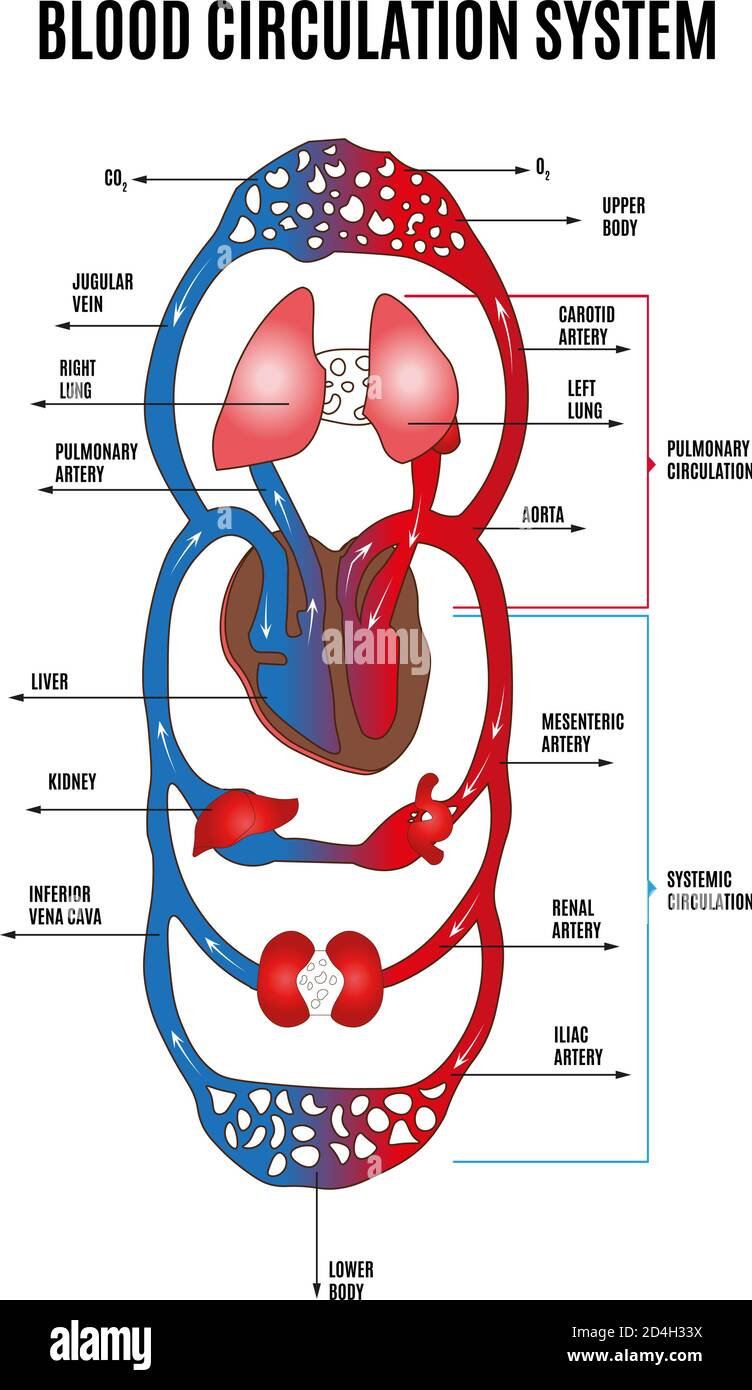

Human circulatory system. Diagram of circulatory system with main parts labeled. Vector illustration of great and small circles of blood circulation Stock Vectorhttps://www.alamy.com/image-license-details/?v=1https://www.alamy.com/human-circulatory-system-diagram-of-circulatory-system-with-main-parts-labeled-vector-illustration-of-great-and-small-circles-of-blood-circulation-image381462366.html

Human circulatory system. Diagram of circulatory system with main parts labeled. Vector illustration of great and small circles of blood circulation Stock Vectorhttps://www.alamy.com/image-license-details/?v=1https://www.alamy.com/human-circulatory-system-diagram-of-circulatory-system-with-main-parts-labeled-vector-illustration-of-great-and-small-circles-of-blood-circulation-image381462366.htmlRF2D4H33X–Human circulatory system. Diagram of circulatory system with main parts labeled. Vector illustration of great and small circles of blood circulation